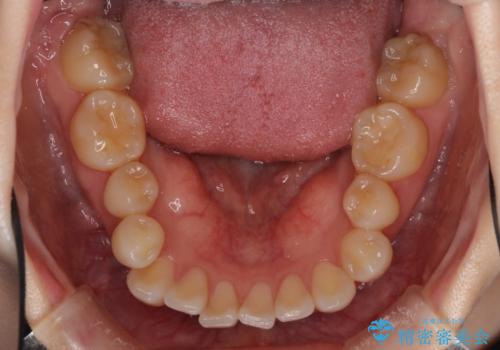

- 前歯のデコボコや八重歯の様になっていることを気にして来院された患者様です。

犬歯捻れて前方に飛び出しており、下顎前歯もそれに沿うようにデコボコとなっていました。

IPR(歯と歯の間を削る処置)によりスペースを獲得して上下顎前歯のデコボコを改善し、前歯が前方に突出しないように設定した上で、インビザラインにて矯正治療を行うこととしました。

途中体調を崩され、長い期間矯正治療を休むことになったため4年半ほどの治療期間がかかりました。